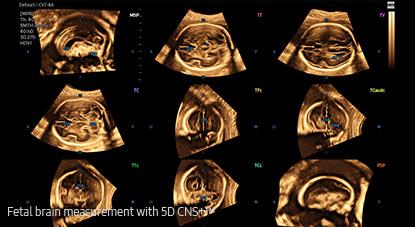

5D CNS+™ ¹ uses intelligent navigation to provide 6 measurements from 3 transverse views of the fetal brain to enhance measurement reproducibility and streamlined workflow.